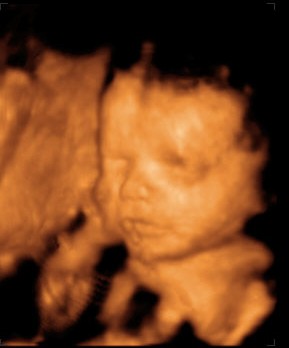

Érdekesség ként:ime egy pár kép a bébinkről. Mert úgye elmentünk Dunakeszi Kenguruba 4D felvételre...ésssss.nem bántuk meg. A csajszikánkba már most szerelmes vagyok: és hát apja lánya, talán az orrocskája az enyém.

25+2 Kép Kép

Hihetetlenül cuki a kicsi lányod!!! Tényleg jól látszik a pofija. Jó érzés, nem?! Én mindig hordom magamnál a 4d-s képet.... a kórházba is vittem...:)